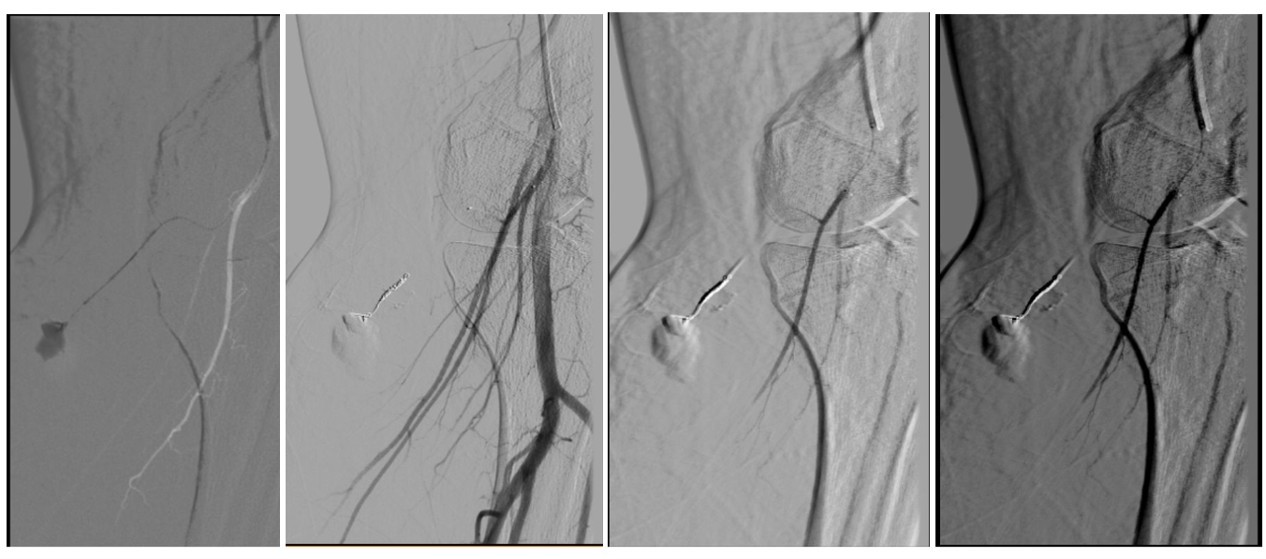

A las cuarenta y ocho horas del postoperatorio el paciente consultó por un cuadro de inflamación infrapatelar de la pierna izquierda. Ante la sospecha de una trombosis venosa profunda, se lo derivó de forma urgente a la guardia, donde se le realizó un ecodoppler venoso. El estudio descartó un proceso flebotrombótico, pero evidenció un hematoma que contenía signos compatibles con un pseudoaneurisma dentro del hematoma (Figs. 1 y 2). Frente a este hallazgo, se decidió realizar de manera urgente una angiografía del miembro inferior izquierdo, la cual confirmó la presencia de un pseudoaneurisma en una rama de pequeño calibre de la arteria poplítea, secundario a laceración traumática de dicho vaso (Fig. 3). En el estudio hemodinámico no se evidenció extravasación de contraste a nivel del pseudoaneurisma, motivo por el cual el equipo de hemodinamia lo consideró indemne.

Figura 1. Ecodoppler con flujo de remolinos representado en colores (Yin y Yang)

Figura 2. Ecodoppler, en la parte inferior se observa la curva de flujo en vaivén, en el cuello del pseudoaneurisma. Lo marcado en rojo es el punto donde se detecta el flujo